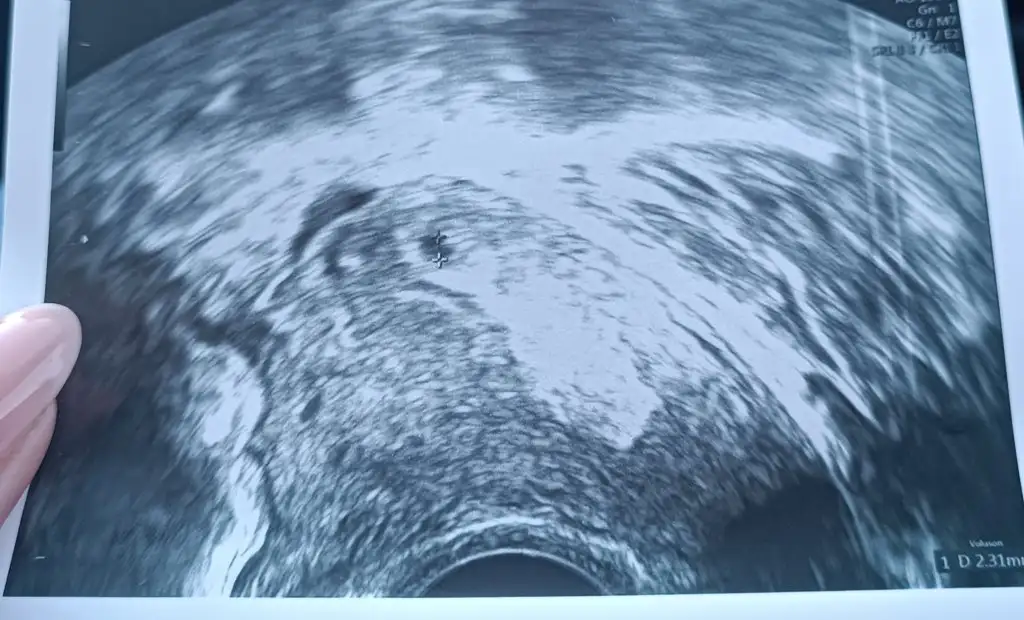

Canım gözün aydın minnak keseyi görmüşsün az kalsın kızını diyecektimEki Görüntüle 3225973 daha çok çok küçükmüş ama muhtemel kese bu dedi![]()

İnsallah canımAy gözünüz aydın kızlarKese görmek için darısı başımıza. Ben yarın gideceğim vajinal ultrasonla bakacak muhtemelen. Lekelenmem devam ediyor. Salı günü 316 idi beta hcg. İlk günler yaşadığım sol kasık ağrısı gaz spazmıymış şu an daha rahatım

Yani adetim 8. Günü şuan da 3. Gününde 122’diKızlar betam 5 günde 122 den 1128’e çıktı nasıl sizcedoktoruma attım yanıt bekliyorum

Çok iyi benceKızlar betam 5 günde 122 den 1128’e çıktı nasıl sizcedoktoruma attım yanıt bekliyorum

Çok çok güzel artmış değerin canım maşallahKızlar betam 5 günde 122 den 1128’e çıktı nasıl sizcedoktoruma attım yanıt bekliyorum